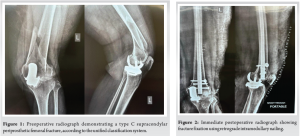

A 63-year-old woman underwent a cemented, mobile-bearing Oxford Phase 3 UKA in 2021, performed by the senior author, for anteromedial osteoarthritis of the left knee. Her post-operative recovery was uneventful. Nine months later, she sustained a high-impact injury in a vehicular accident. Radiographic evaluation revealed a supracondylar, extra-articular periprosthetic femoral fracture, classified as Type C according to the Unified Classification System (UCS) [7] (Fig. 1). There was no evidence of ligamentous instability. Both femoral and tibial components appeared well-fixed, and no polyethylene insert dislocation was observed on imaging.

The patient underwent retrograde intramedullary nailing (RIMN) for fracture fixation (Fig. 2). Her pre-injury Oxford Knee Score (OKS) was 48. Following fracture healing, her OKS decreased to 40. Active and passive range-of-motion exercises were initiated immediately after surgery. At 12 weeks postoperatively, radiographs confirmed fracture union, and full weight-bearing ambulation was permitted. By 5 months postoperatively, the patient had regained a full range of motion (130°), was able to sit cross-legged, and walked independently (Fig. 3 and 4). At 2½ years after fracture fixation, the UKA components remained well-fixed, and the patient’s OKS was 32 (Fig. 5).